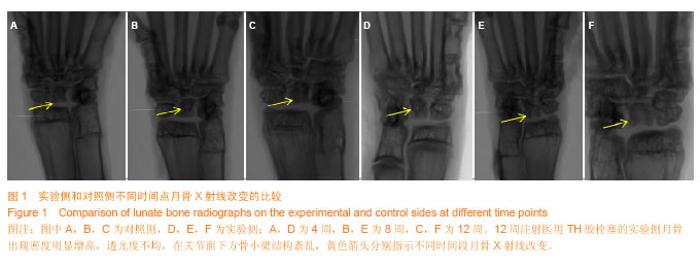

METHODS:A total of 30 healthy adult New Zealand rabbits, male or female, were selected. Using self-control method, the rabbits were randomly assigned to experimental sides and control sides. By drilling in the center of the lunate bone, 0.2 mL of medical TH glue was injected three times. An equal volume of physiological saline was injected into the center of the lunate bone on the control side. X-ray examination, general observation, Micro-CT measurement of bone, and tissue pathology detection were conducted at 4, 8 and 12 weeks.

RESULTS AND CONCLUSION:Gross specimen, X-ray and histological results showed that ischemic necrosis of the lunate bone on the experimental side was visible at 8 weeks after model induction. The ischemic necrosis of the lunate bone became more typical at 12 weeks. Among the Micro-CT microscopic parameters of trabecular bone, trabecular bone density parameters bone volume fraction and the number of trabecular bone were significantly lower on the experimental side than those on the control side (P < 0.05). Spatial parameters of trabecular bone significantly increased. Trabecular separation and structure model index on the experimental  side were significantly greater than those on the control side. Results suggested that ischemic necrosis of the lunate bone appeared on the experimental side at 8 weeks after injection of medical TH glue. Rabbit models of ischemic necrosis of the lunate bone can be established at 12 weeks. Thus, alterations, which were similar to ischemic necrosis of human lunate bone, appeared, such as blood transportation damage in the lunate bone, trabecular bone fracture, and empty lacuna, when surrounding tissues were not obviously injured.